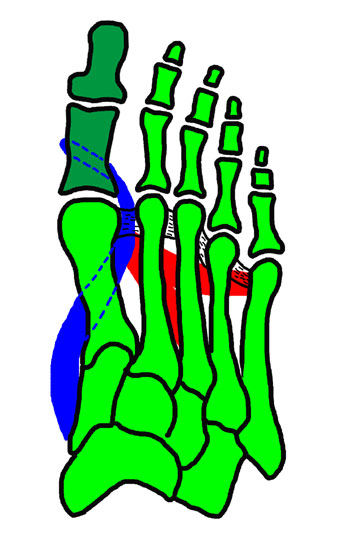

Einfluß von Korrekturen des MT I- Schaftes auf die Stellung des MTP I (Hefti ,1998)

Abbildung 8

Falls die knöcherne Korrektur des Os Metatarsale I im Rahmen einer Voroperation zu einem sehr kleinen oder sogar negativen IM-Winkel und einem daraus resultieren Hallux varus geführt hat, muss die Stellung des Metatarsale I nach medial reorientiert werden, oft verbunden mit einem zusätzlichen Sehnentransfer.

Oft führt auch eine leichte Verkürzung des Os metatarsale 1 (z. B. mittels Scarf-Osteotomie) zu einer Entspannung der intrinsischen Muskulatur und somit einer verbesserten Ausrichtung der Großzehe (Sabo, 2012).